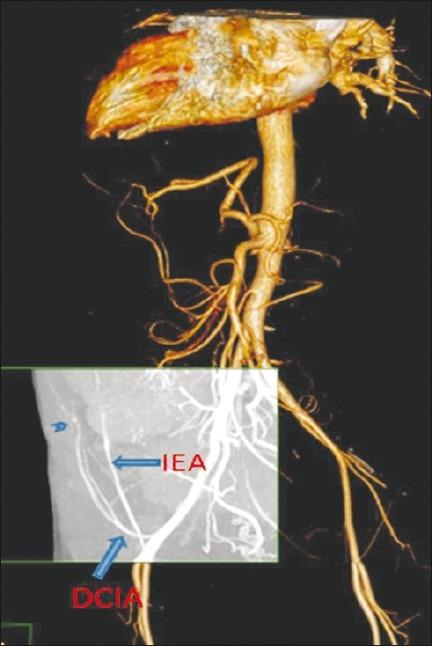

We report a case of a pseudoaneurysm arising from the deep circumflex iliac artery, in an end-stage renal disease patient with gross ascitis, presenting with an anterior abdominal wall hematoma following paracentesis. Duplex Doppler sonography confirmed the presence of the pseudoaneurysm and multidetector computed tomography angiography delineated the detailed arterial anatomy.

我们报告一例终末期肾病合并大量腹水患者,其髂外深动脉出现假性动脉瘤,在腹腔穿刺术后出现前腹壁血肿。双功多普勒超声检查证实了假性动脉瘤的存在,多排计算机断层扫描血管造影描绘了详细的动脉解剖结构。